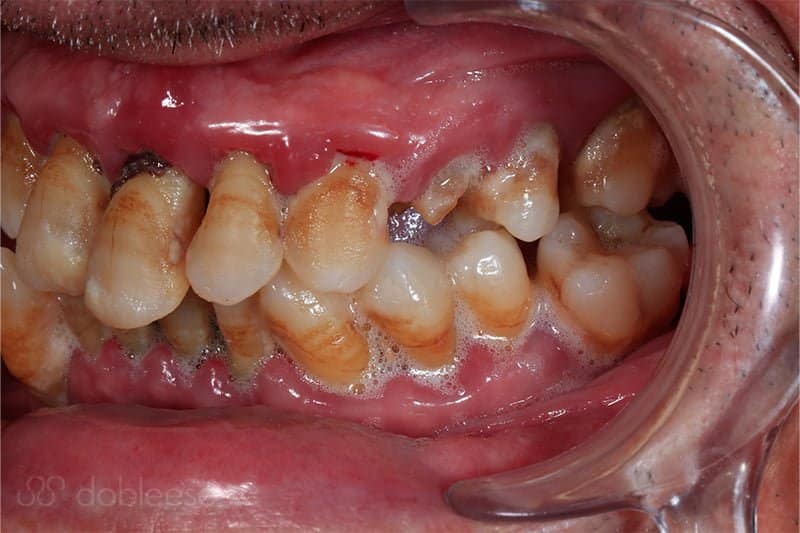

Juan Ramón llegó a nuestra clínica tras recibir la recomendación de un familiar, al que le hicimos un tratamiento muy parecido. Llegó a Dobleese con tanta movilidad en las piezas dentales, que no podía comer con normalidad porque sufría el riesgo de perderlas al masticar alimentos duros.

Al estudiar su caso, observamos que tenía una enfermedad periodontal muy agravada con gran pérdida de hueso alrededor de los dientes, motivo por el cual se le movían tanto. Por ello, concluimos que no podíamos mantener ninguna de las piezas dentales, ya que todas estaban en mal estado, con infección y con una pérdida de soporte imposible de recuperar.